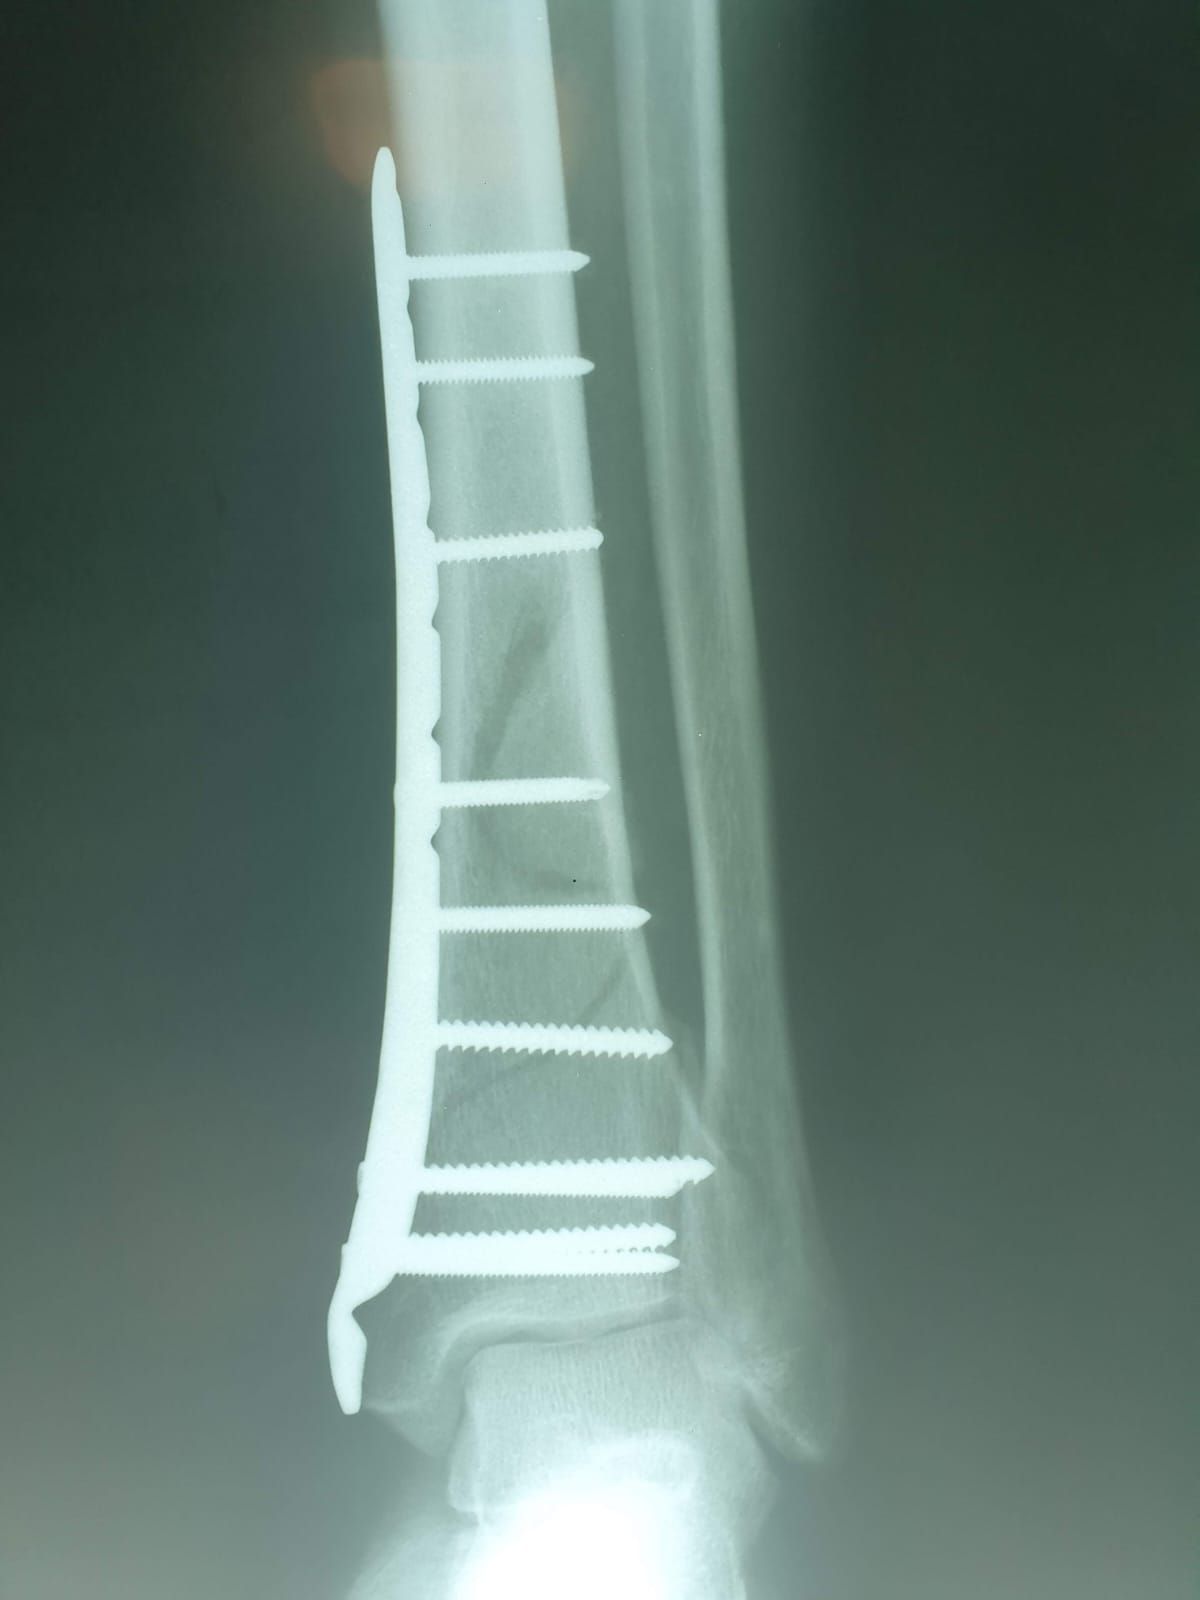

Fotos y videos